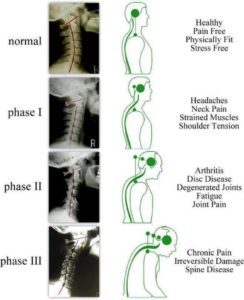

Il-proċess deġenerattiv tad-diski intervertebrali ġie maqsum fi tliet stadji, skond Kirkaldy-Willis u Bernard, imsejħa "kaskata deġenerattiva". Dawn l-istadji jistgħu jikkoinċidu u jistgħu jseħħu matul għexieren ta 'snin. Madankollu, l-identifikazzjoni ta 'dawn l-istadji klinikament mhix possibbli minħabba l-irduppjar ta' sintomi u sinjali.

Stadju 1 (Fażi ta 'deġenerazzjoni)

Dan l-istadju huwa kkaratterizzat minn deġenerazzjoni. Hemm tibdil istoloġiku, li juri dmugħ ċirkonferenzjali u fissuri fil-annulus fibrosus. Dawn id-dmugħ ċirkonferenzjali jistgħu jinbidlu fi dmugħ radjali u minħabba li l-annulus pulposus huwa nnervat sew, dawn id-dmugħ jistgħu jikkawżaw uġigħ fid-dahar jew uġigħ fl-għonq, li huwa lokalizzat u bi movimenti ta 'uġigħ. Minħabba trawma ripetuta fid-diski, l-endplates jistgħu jisseparaw u jwasslu għat-tfixkil tal-provvista tad-demm għad-diska u għalhekk, iċaħħduha mill-provvista ta 'nutrijenti tagħha u tneħħi l-iskart. L-annulus jista 'jkun fih mikro-fratturi fil-fibrils tal-kollaġen, li jistgħu jidhru fuq il-mikroskopija elettronika u skan tal-MRI jista' jiżvela dessikazzjoni, intelliġenza tad-diska, u żona ta 'intensità għolja fl-annulus. Il-ġogi tal-faċċati jistgħu juru reazzjoni sinovjali u jistgħu jikkawżaw uġigħ qawwi ma 'sinovite assoċjata u l-inkapaċità li tiċċaqlaq il-ġogi fil-ġogi zapapophyseal. Dawn il-bidliet jistgħu mhux neċessarjament iseħħu f'kull persuna. (Gupta, Vijay Kumar, et al.)

Stadju 2 (Fażi ta 'Instabbiltà)

L-istadju ta 'disfunzjoni huwa segwit minn stadju ta' instabilità, li jista 'jirriżulta mid-deterjorament progressiv tal-integrità mekkanika tal-kumpless tal-ġonta. Jista 'jkun hemm diversi bidliet li nqalgħu f'dan l-istadju, inkluż interruzzjoni u riassorbiment tad-diska, li jistgħu jwasslu għal telf ta' għoli ta 'spazju fid-diska. Jistgħu jseħħu diversi dmugħ annulari f'dan l-istadju ukoll b'bidliet fl-istess ħin fil-ġogi zagopophyseal. Jistgħu jinkludu deġenerazzjoni tal-qarquċa u laxkezza kapsulari tal-faċċati li twassal għal subluxation. Dawn il-bidliet bijomekkaniċi jirriżultaw fl-instabilità tas-segment affettwat.

Stadju 3 (Fażi ta 'Stabbilizzazzjoni mill-ġdid)

F’dan it-tielet u l-aħħar stadju, id-deġenerazzjoni progressiva twassal għal restrizzjoni tal-ispazju tad-diska bi fibrożi u formazzjoni ta ’osteofiti u pont transdiskali. L-uġigħ li joħroġ minn dawn il-bidliet huwa gravi meta mqabbel maż-żewġ stadji preċedenti, iżda dawn jistgħu jvarjaw bejn l-individwi. Dan id-djuq tal-ispazju tad-diska jista 'jkollu diversi implikazzjonijiet fuq is-sinsla. Dan jista 'jikkawża li l-kanal intervertebrali jonqos fid-direzzjoni superjuri-inferjuri bl-approssimazzjoni tal-pedikoli ta' maġenb. Ligamenti lonġitudinali, li jappoġġjaw il-kolonna vertebrali, jistgħu wkoll isiru defiċjenti f'xi oqsma li jwasslu għal-lassità u l-instabilità tas-sinsla. Il-movimenti ta 'l-ispina jistgħu jikkawżaw il-ligum tal-flavum biex jintefgħu u jistgħu jikkawżaw subluxation tal-proċess superjuri. Dan fl-aħħar iwassal għal tnaqqis tad-dijametru fid-direzzjoni anteroposterior ta 'l-ispazju intervertebrali u stenożi ta' l-għeruq tan-nervituri ta 'fuq.

Dawn il-bidliet kollha jwasslu għal uġigħ fid-dahar baxx, li jonqos bis-severità. Sintomi oħra bħal moviment imnaqqas, sensittività fil-muskoli, ebusija, u skoljożi jistgħu jseħħu. Iċ-ċelloli staminali sinovjali u l-makrofaġi huma involuti f'dan il-proċess billi jirrilaxxaw fatturi ta 'tkabbir u molekuli ta' matriċi extraċellulari, li jaġixxu bħala medjaturi. Ir-rilaxx ta 'ċitokini nstab li huwa assoċjat ma' kull stadju u jista 'jkollu implikazzjonijiet terapewtiċi fl-iżvilupp ta' trattament futur.